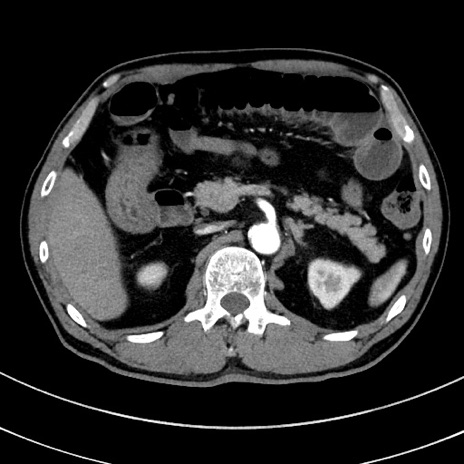

冠状断像